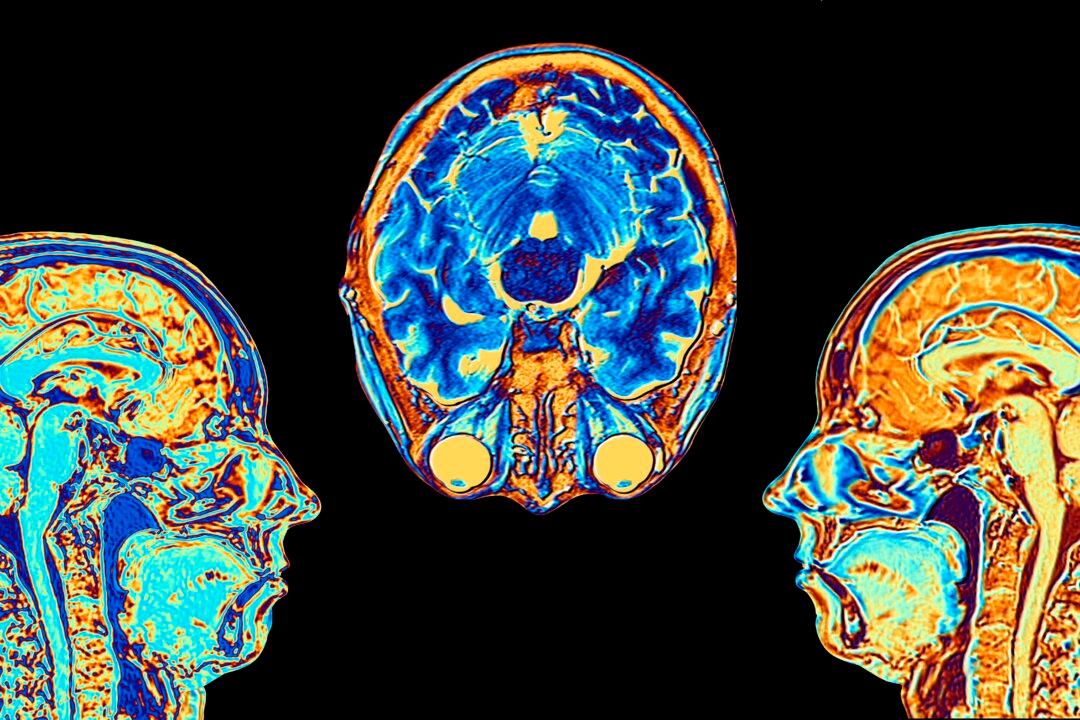

The U.S. Food and Drug Administration (FDA) has approved Voranigo, a new drug from the French pharmaceutical firm Servier, for the treatment of a type of brain cancer.

It is the first treatment in the United States to be approved by the FDA for treating a form of brain cancer, called Grade 2 IDH-mutant glioma, in patients who have had surgery.